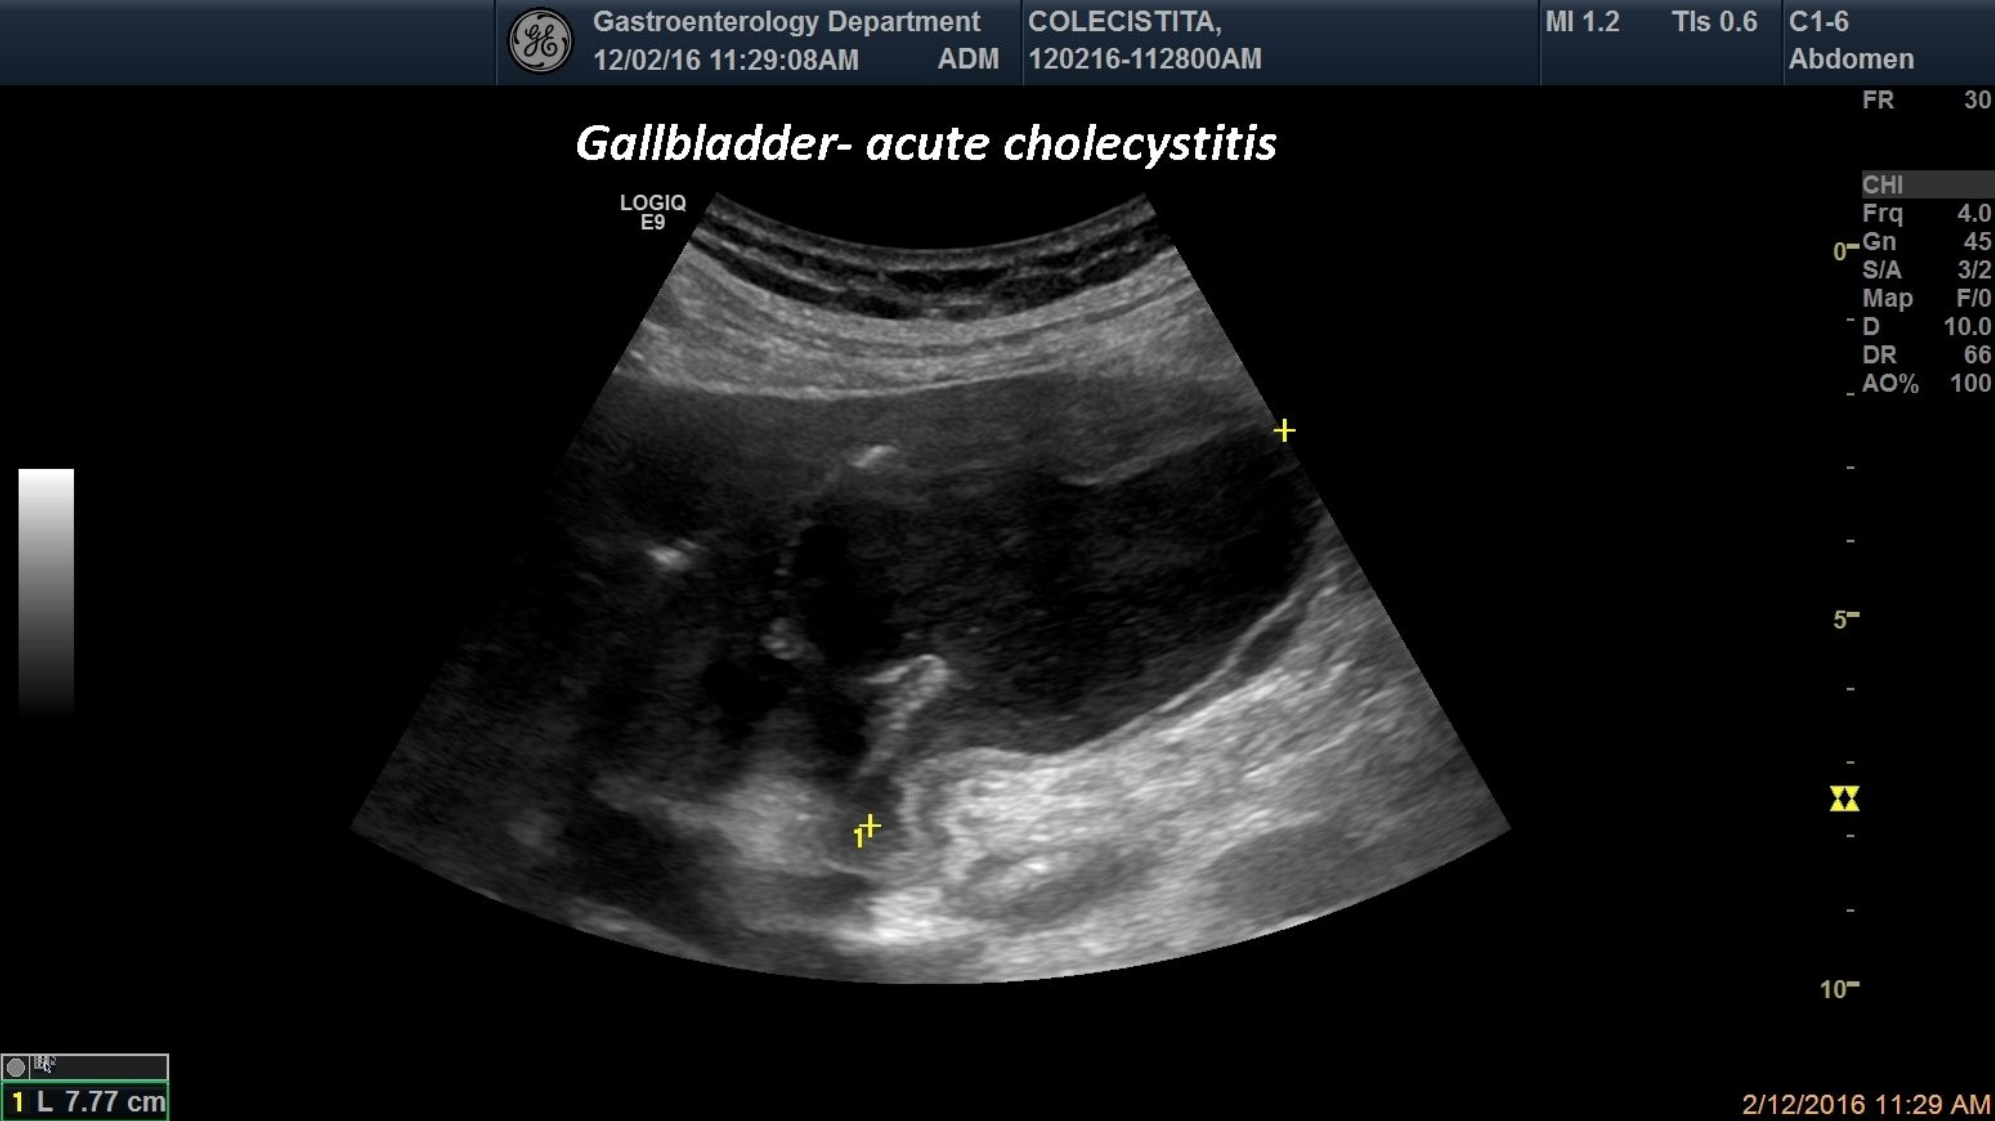

An 68-year-old patient was brought into the emergency room for acute abdominal pain and a positive Murphy sign. Ultrasound examination has revealed an enlarged gallbladder with thick (edema) and duplicated gallbladder walls, highly suspicious for the diagnosis of acute cholecystitis.The diagnosis was confirmedlater on by surgery.